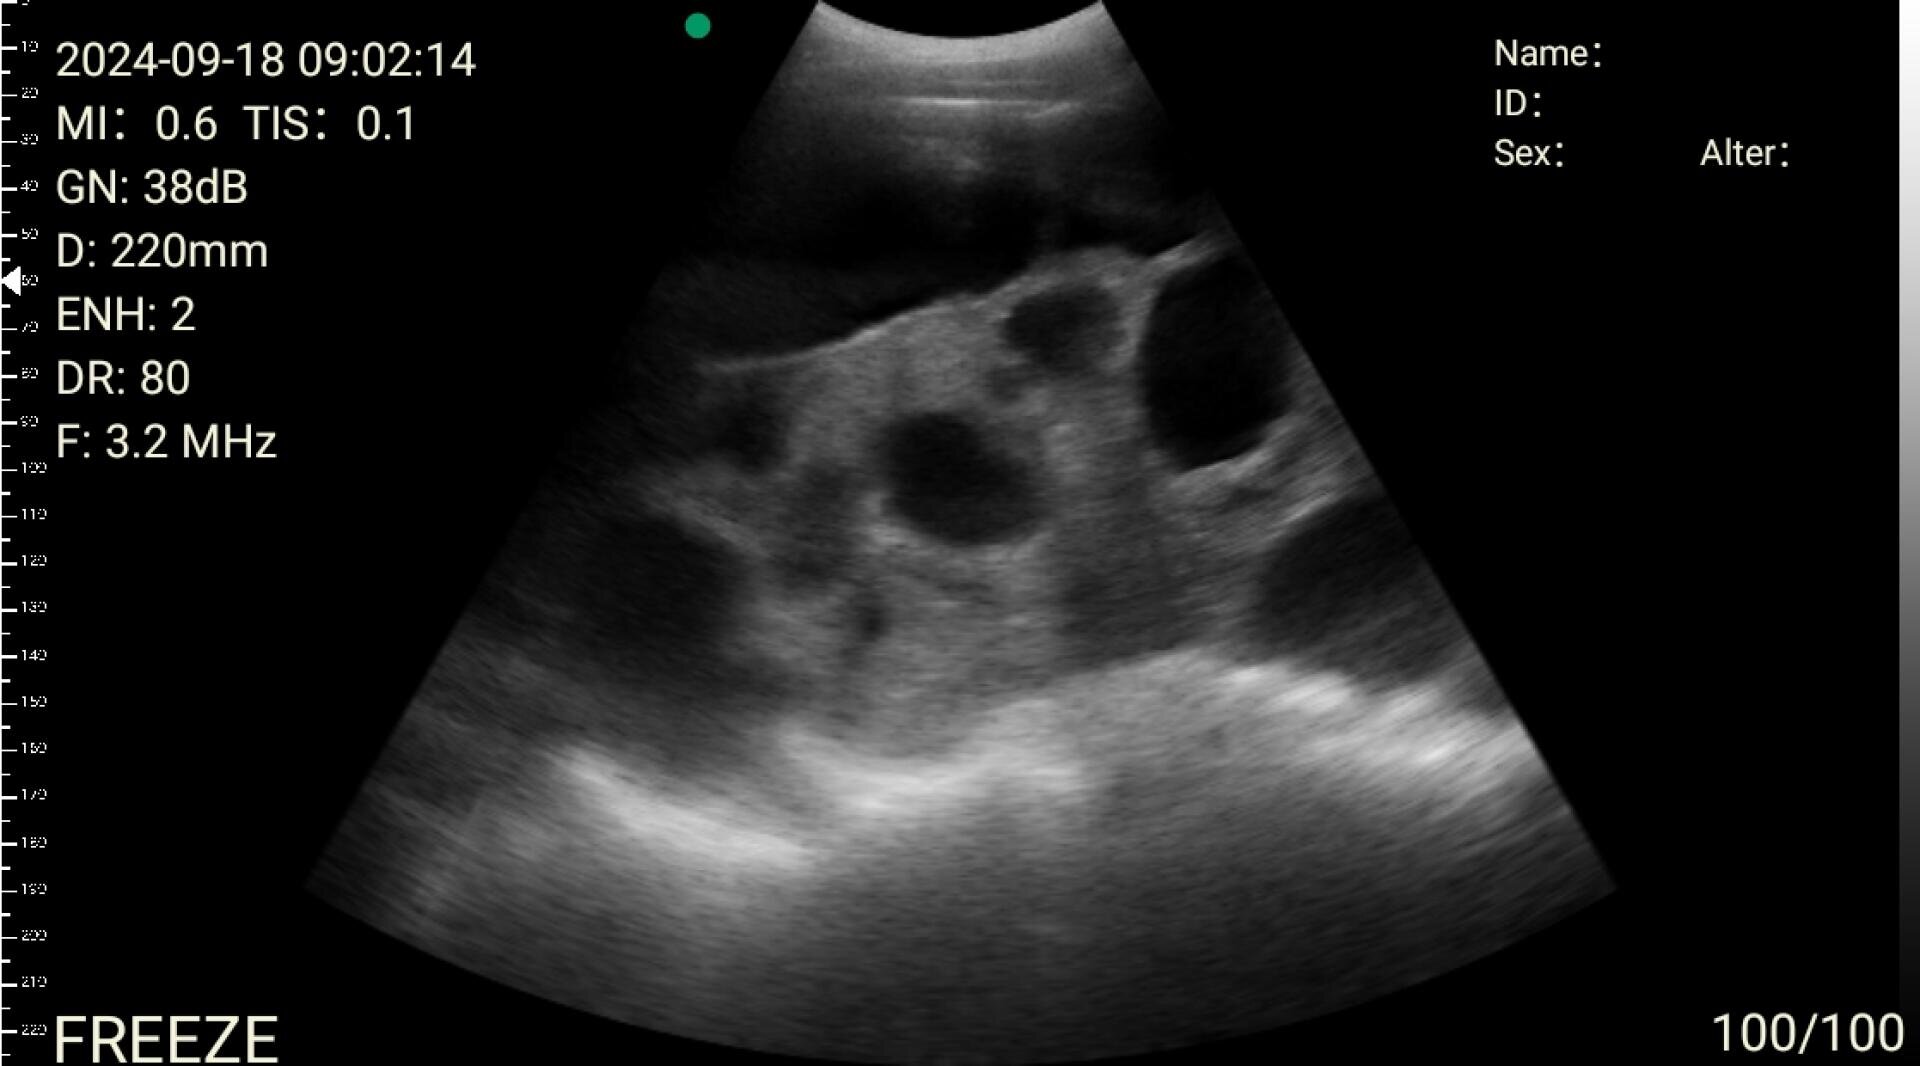

Trächtigkeitskontrolle gibt Sicherheit

Eine lückenlose Trächtigkeitskontrolle gibt guten Überblick auf den Trächtigkeitserfolg und gehört zu einem zeitgemässen, erfolgreichen Herdenmanagement.

Als Produzenten-Organisation stimmen wir unsere Dienstleistungen auf die Bedürfnisse unserer Züchter und Mäster ab. Somit kann ein Profera-Produzent situationsgerecht eine qualifizierte Beratung oder Dienstleistung von Profera in Anspruch nehmen. Im Zusammenhang mit den saisonal höheren Temperaturschwankungen steigt das Umrauscher-Risiko bei Remonten und Muttersauen. Eine zeitgerechte Trächtigkeitskontrolle gibt einen sehr guten Überblick in Bezug auf den Trächtigkeitserfolg und das Herdenmanagement insgesamt.